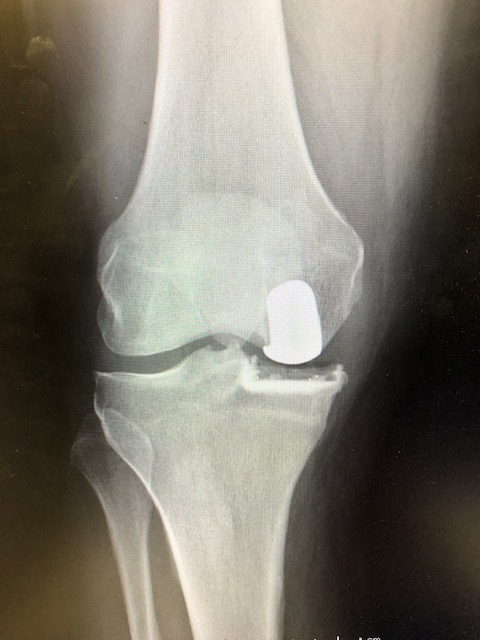

Here are some pictures of MIPKR